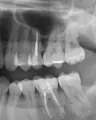

Недавно поставил металлокерамическую коронку на передний зуб верхней челюсти, а сейчас появилась на нёбе шишечка (в виде мозоля). Сделал рентген зуба, показало кисту, как врач сказал приличного размера, что уже поразило костную ткань и достаёт на небо.

Когда ставили коронку зуб лечили. Не знаю, почему врач тогда не заметил кисту (снимки делал два раза), залечили, поставил коронку, а теперь вот проблемы - киста.